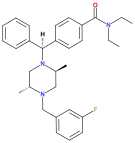

Diphenylmethylpiperazines